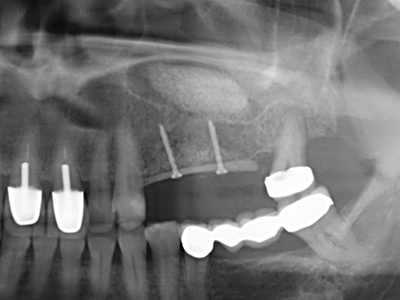

Фиг. 11: Следоперативната панорамна снимка показва вертикалната аугментация и синус лифта.

Фиг. 15: Прегледът на рентгеновата снимка след 1 година показва стабилно състояние на нивото на костта.